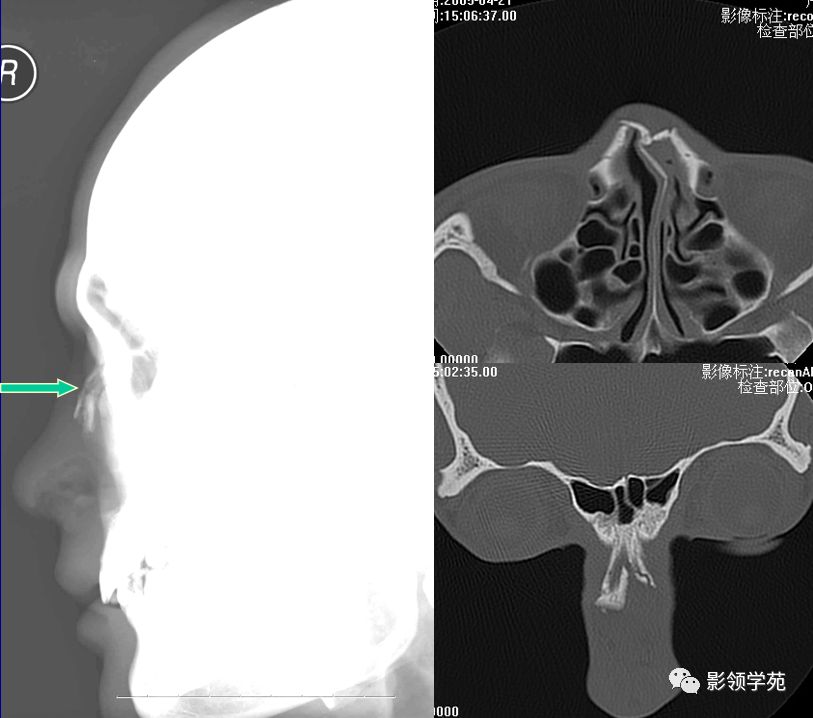

HRCT

- 冠状面:鼻骨长轴平行线

鼻骨冠状面HRCT